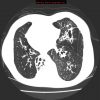

– Giãn phế quản (Bronchiectasis) là giãn không hồi phục một phần của cây phế quản và thường đi kèm với hiện tượng dày thành phế quản và ứ đọng chất nhầy. Có thể giãn ở phế quản lớn trong khi phế quản nhỏ vẫn bình thường hoặc giãn ở phế quản nhỏ trong khi phế quản lớn bình thường.

– Bình thường khẩu kính phế quản ngang với khẩu kính động mạch đi kèm. Trường hợp giãn phế quản, khẩu kính của phế quản sẽ lớn hơn động mạch đi kèm.

– Giãn dạng khu trú hay gặp nhất. Thường gặp ở các phân thùy đáy sau (50%), thùy giữa hoặc thùy lưỡi (10%)